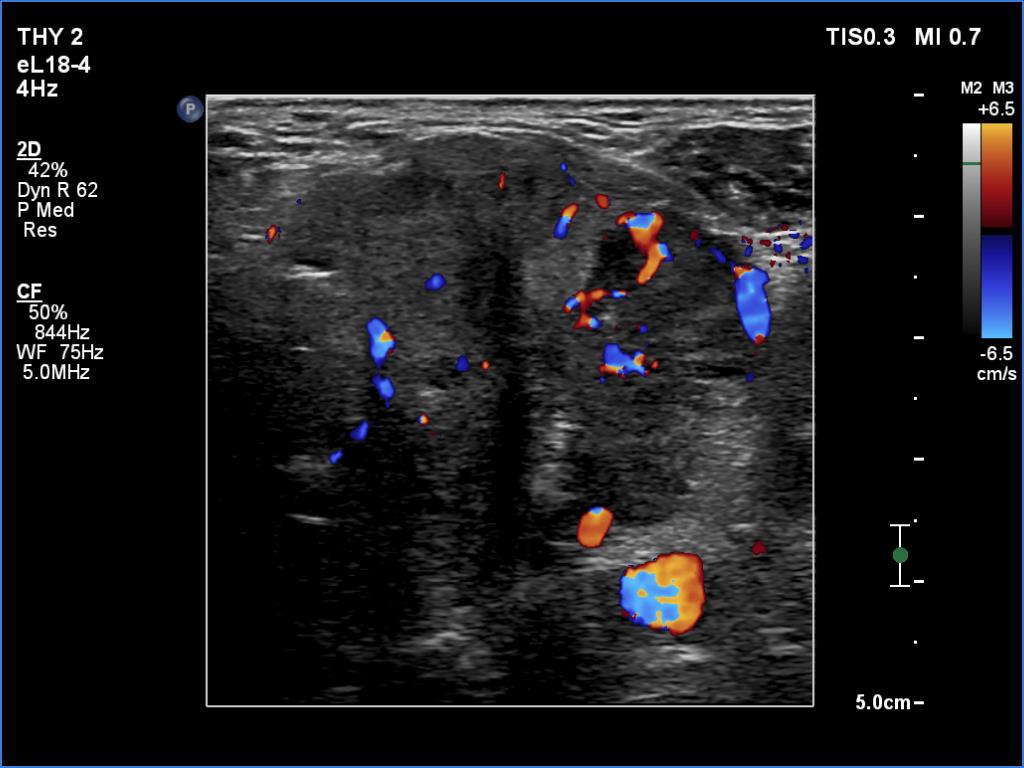

Ultrasonography. The right lobe was echonormal and intact. A large mass occupied almost the entire left lobe. On this side, normal thyroid tissue could only be identified in the dorsal part. The mass was composed of echonormal and hypoechoic areas, had macrocalcifications, irregular intranodular vascularity and proved to be very hard on elastography. There were multiple lymph nodes in III, IV and V left neck compartments. One of the nodes was in close proximity to the jugular vein and was suspicious of having broken into the vessel. The trachea was significantly narrowed at the lower level of the thyroid.

2. There are several remarkable findings in this case, e.g., the destruction of the left lobe by the tumor, the elastography pattern, the relation of the largest metastatic lymph node and the jugular vein, the ultrasound demonstration of the trachea' stricture.